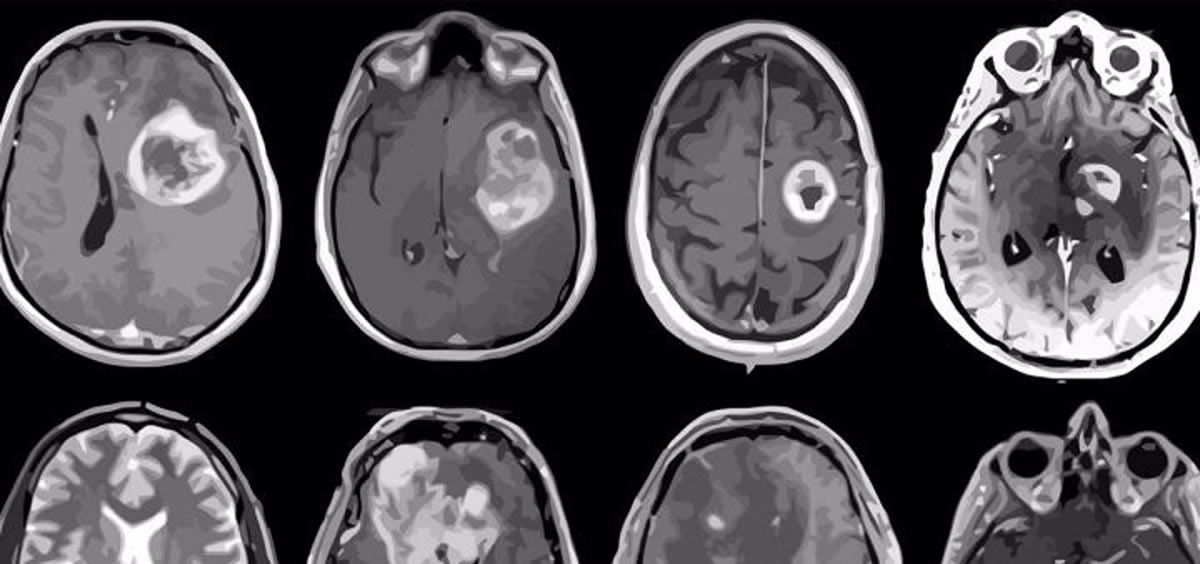

La inteligencia artificial (IA) ha servido para desarrollar un sistema de diagnóstico para analizar muestras tumorales. Un equipo de neurocirujanos e ingenieros de varias universidades estadounidenses ha desarrollado este sistema, con el que la IA utiliza imágenes rápidas para examinar las muestras tomadas durante una operación. Así, detecta mutaciones genéticasen menos de 90 segundos.

En un estudio de más de 150 pacientes con glioma difuso, el tumor cerebral primario más común y mortal, el sistema recién desarrollado identificó mutaciones utilizadas por la Organización Mundial de la Salud (OMS) para definir subgrupos moleculares de la afección con una precisión media superior al 90 por ciento.

La clasificación molecular es cada vez más importante para el diagnóstico y tratamiento de los gliomas, ya que los beneficios y riesgos de la cirugía varían entre los pacientes con tumores cerebrales en función de su composición genética.

Antes de este sistema, denominado 'DeepGlioma', los cirujanos no tenían un método para diferenciar los gliomas difusos durante la cirugía. El sistema, una idea que comenzó en 2019, combina redes neuronales profundas con un método de imagen óptica para obtener imágenes del tejido tumoral cerebral en tiempo real.